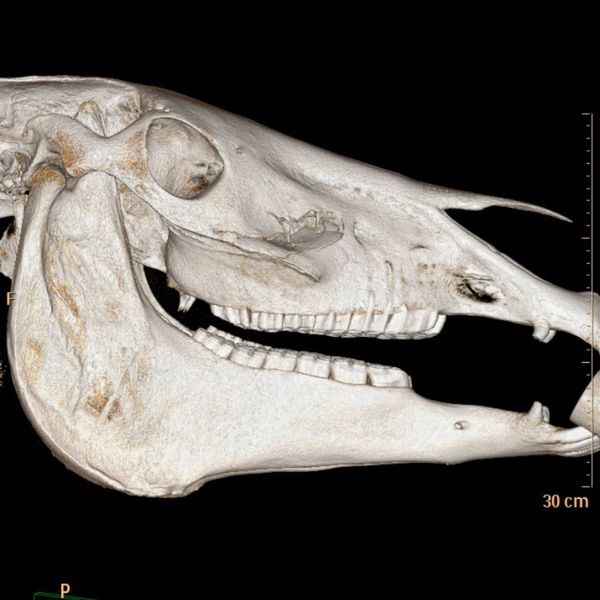

Hard Tissue Mastery: Digital Radiography for Horses

When we need to look at the "scaffolding" of your horse, we turn to digital radiography for horses. This technology is the gold standard for evaluating bones. If you suspect a fracture, or if your horse is showing signs of chronic lameness, X-rays allow us to see structural changes clearly. It is particularly effective for identifying equine bone spurs on X-ray, as well as osteoarthritis or developmental orthopedic diseases. Because our system is digital, we can capture high-resolution images right in the barn or clinic, providing instant feedback on your horse's skeletal health.